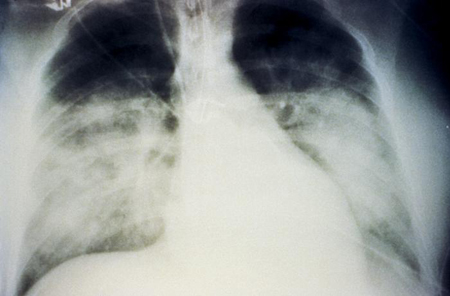

Investigation with FBC, CXR, and arterial blood gas (ABG) are required. The FBC shows haemoconcentration, as indicated by an elevated Hb and Hct. This is a marker for capillary leak. CXR shows evidence of progressive non-cardiogenic pulmonary oedema (the heart size remains normal and pulmonary infiltrates ± pleural effusion may be present). [Figure caption and citation for the preceding image starts]: Bilateral fluffy pulmonary infiltrates in hantavirus pulmonary syndromeCDC Public Health Image Library (PHIL), Loren Ketai, MD [Citation ends].com.bmj.content.model.Caption@65b0efb1 ABG shows a metabolic acidosis. Serum lactate should be performed, as elevated levels are a marker of poor outcome.